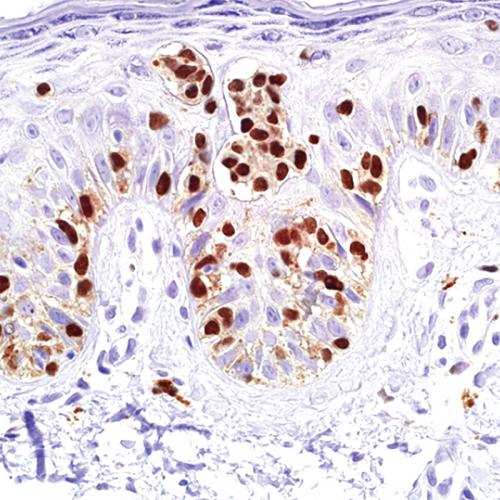

雙染技術(shù)是目前常用的免疫組化染色方法之一,由于可以在一張切片上同時顯示兩種不同的抗原,為病理診斷和科研提供了更加直觀和詳實的依據(jù)。雙染技術(shù)一般是應(yīng)用兩種不同動物種屬來源的抗體,如分別為小鼠來源的一抗和兔來源的一抗。該試劑盒是基于聚合物技術(shù)的非生物素檢測系統(tǒng),由辣根過氧化物酶和堿性磷酸酶兩個染色系統(tǒng)構(gòu)成,兩者之間不會產(chǎn)生相互干擾。堿性磷酸酶的顯色系統(tǒng)為AP-Red,辣根過氧化物酶的顯色系統(tǒng)為DAB,前者顯色為紅色,而后者為棕黃色。